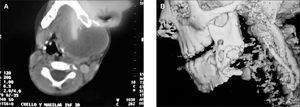

La tomografía computarizada (TC) realizada mostró una lesión de tejidos blandos que comprometía la hemimandíbula izquierda (fig. 2A y B). La biopsia de la lesión confirmó el diagnóstico de fibromixoma de origen odontogénico. Con este diagnóstico, se practicó resección completa macroscópica del tumor con reconstrucción con placa de mandíbula, por el servicio de cirugía plástica (fig. 3A y B).

Figura 2A y B. TC y reconstrucción.